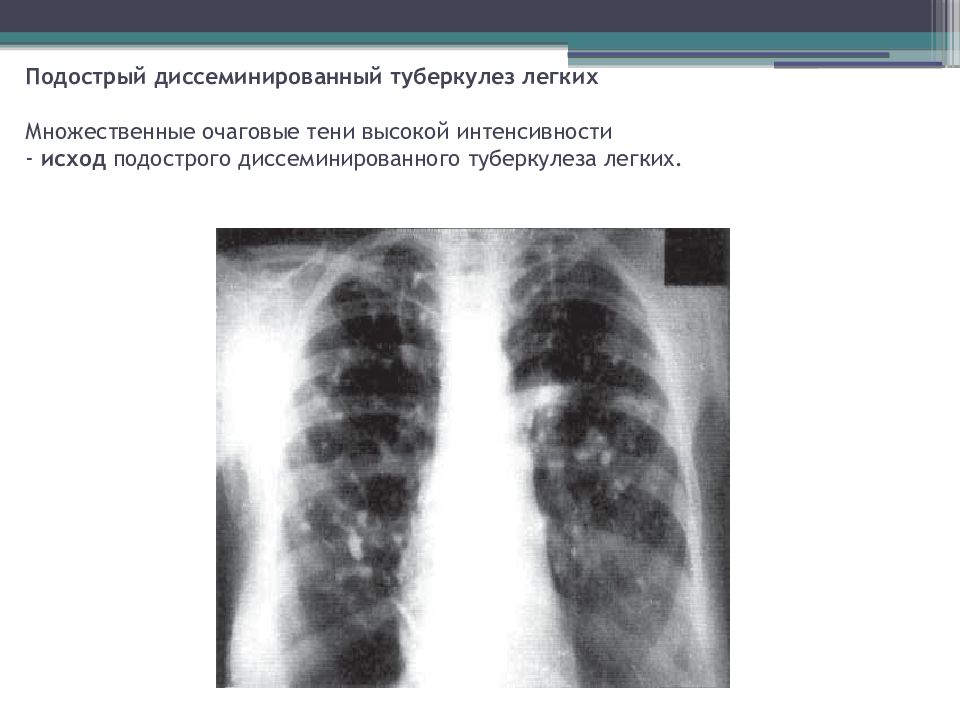

Иллюстрации по теме очагового и инфильтративного туберкулеза

Раздел: Фотодневник открытий